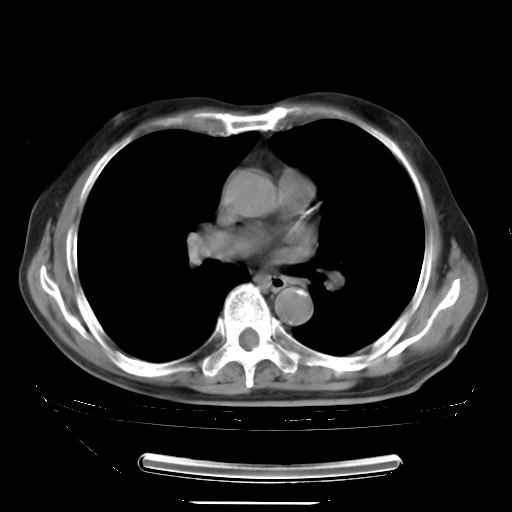

今天复查肺部CT,发现双肺广泛磨玻璃样改变。所以我把3月19日和5月9日相隔50天的肺部CT上传。请大家会诊。

5月9日肺部CT(在4月27日齐鲁医院肺部CT描述部分肺组织磨玻璃样改变,12天后肺组织广泛磨玻璃样改变)

2009年5月9日肺部CT

大致读了系列胸部CT:纵隔窗无明显异常,肺窗:从4、27至今:主要是双肺中下野外带可见毛玻璃样改变,目前处于急性肺泡炎阶段,至于原因考虑1、结替组织或胶原血管性疾病所致?2、恶性疾病如恶组在肺部所致的表现或细支气管肺泡癌?3、药物或其它原因如肺蛋白沉着症所致肺泡炎目前不太可能?总之,明天就去请我院的呼吸科、感染科、血液科和临免专家会诊哈。